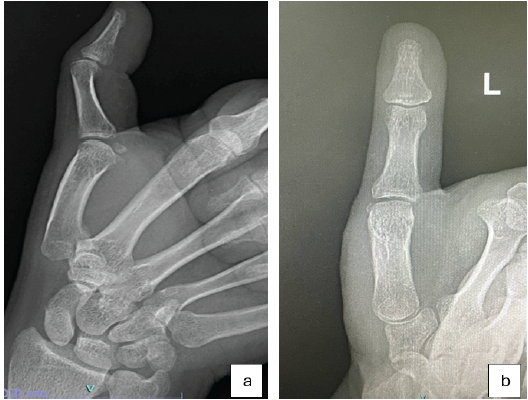

Radiographs revealed a healed fracture at the base of the first metacarpal, which was malunited, and the metacarpal was hinging over the underlying trapezium (Fig. 1a and b). Stress views were not obtained.

Figure 1: (a and b) showing the plain radiographs of base of first metacarpal anteroposterior and lateral views.

Computed tomography with 3D reconstruction showed a displaced intra-articular fracture at base of the first metacarpal involving volar, ulnar aspects of the bone, consistent with Bennett’s fracture attached to the beak ligament, with proximally and laterally migrated distal metacarpal fragment (Fig. 2a and b).

Figure 2: (a and b) showing the pre-operative computed tomography images of the malunited base of first metacarpal.